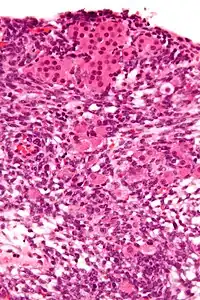

| Micrograph of a Sertoli–Leydig cell tumour. The Leydig cells have abundant eosinophilic or light pink cytoplasm. The Sertoli cells have a pale/clear cytoplasm. H&E stain. | |

Sertoli–Leydig cell tumour is a group of tumors composed of variable proportions of Sertoli cells, Leydig cells, and in the case of intermediate and poorly differentiated neoplasms, primitive gonadal stroma and sometimes heterologous elements.[1]

The tumour is subdivided into many different subtypes. The most typical is composed of tubules lined by Sertoli cells and interstitial clusters of Leydig cells.